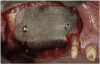

Figure 5  Titanium mesh/particulate graft complex.

Figure 5

Figure 7  Post-augmentation alveolar ridge width net gain of 7 mm (7 months).

Figure 7